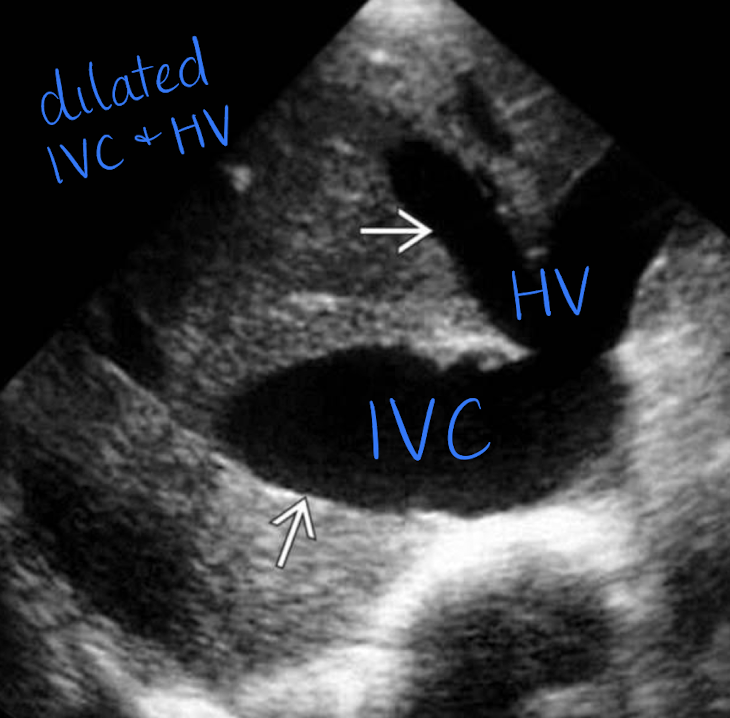

IVC pathology

right ventricular failure (causes IVC to not collapse during inspiration or expiration)

IVC and HV dilation